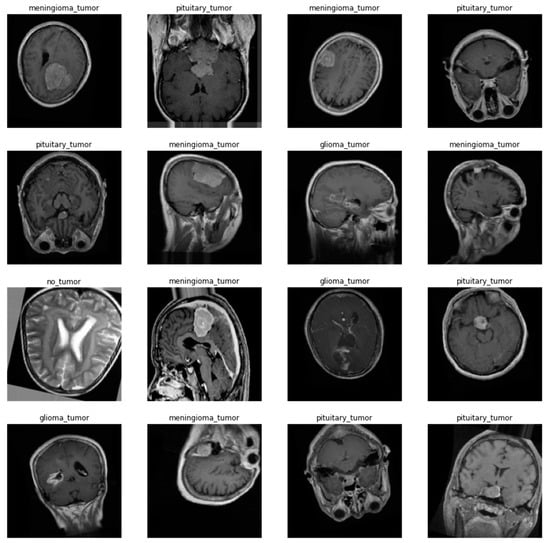

The dataset used for training came from the Kaggle platform and was created by Sartaj Bhuvaji et al. [9]. It consists of images coming from different internet sources that were collected, filtered, and annotation-checked by authors and then published under the Creative Commons 1.0 license. The dataset contains 3264 images from four categories: no_tumor (500), pituitary_tumor (901), glioma_tumor (926), and meningioma_tumor (937). Images come in all three different cross-sections: Sagittal, Coronal, and Transverse planes, although the dataset is not balanced regarding the type of plane visible on the image, and they are not labeled with that information. All the images are grayscale, and their resolution varies from 167 × 174 to 1446 × 1375 pixels, but the most common resolution is approximately 500 × 500 pixels.

Before training networks, all the images were processed with a set of operations: rescaling to the size of 160 × 160 pixels, normalization to the (0, 1) interval, and addition of one-hot encoding annotation; every image was paired with a four-element vector of zeros and a single one, indicating from which class the image comes. The dataset was then split into training and testing in a proportion of 70%:30%, and the training dataset was subjected to data augmentation with operations: random rotation in the range of (−15,15) degrees, vertical and horizontal translation up to 10% of image’s size, and vertical and horizontal flips. The test dataset was not augmented. A few random samples from the training dataset are shown in Figure 5.

Figure 5. Samples from the training dataset with annotations. Augmented data.

Applsci 12 11880 g005